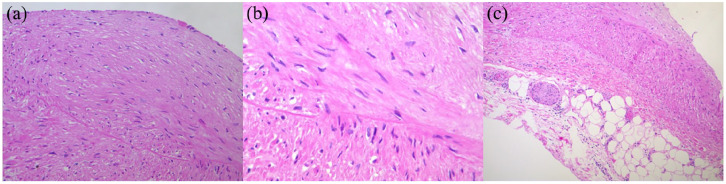

Atherosclerosis is a complex disease characterized by the accumulation of plaques in arterial walls. Understanding its pathogenesis remains incomplete, with factors like inflammation, oxidative stress, and hypertension playing critical roles. The disease exhibits preferential localization of plaques, with variability observed even within the same individual. Genetic, environmental, and lifestyle factors contribute to its heterogeneity. Histological plaque phenotypes vary widely, prompting classification schemes focusing on systemic and local factors deteriorating fibrous caps. Recent research highlights differences in plaque histology among arterial systems, suggesting unique pathophysiological mechanisms. This study reports on multiple atherosclerotic plaques detected at autopsy in various vascular sites of a single subject, emphasizing their histological diversity and underscoring the systemic nature of atherosclerosis.

Abstract Image